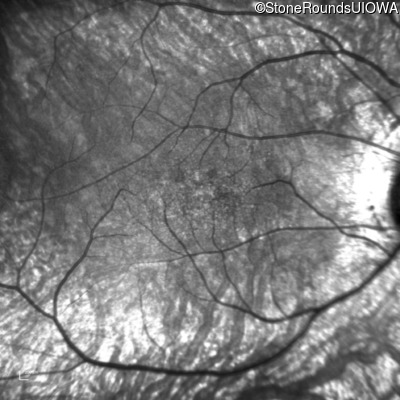

Infrared Fundus Photograph - Right - 20/80 sc

Exemplar